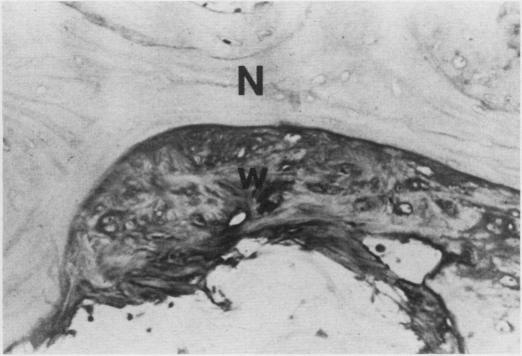

Necrosis of intramedullary bone and bone marrow elements is reported in the long bones of a dog. Radiographically lesions were evident as an irregular increase in intramedullary density. On gross postmortem examination necrotic tissue appeared as yellow-white deposits on the endosteal surface and in the medullary cavity. Microscopically, necrotic bone had empty lacunae and was often covered by basophilic, woven bone. The cause and pathogenesisof aseptic necrosis of bone are discussed.